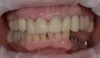

Фото 3: Вид после фиксации временной композитной коронки. Визуализация активной фистулы в области 11 зуба.